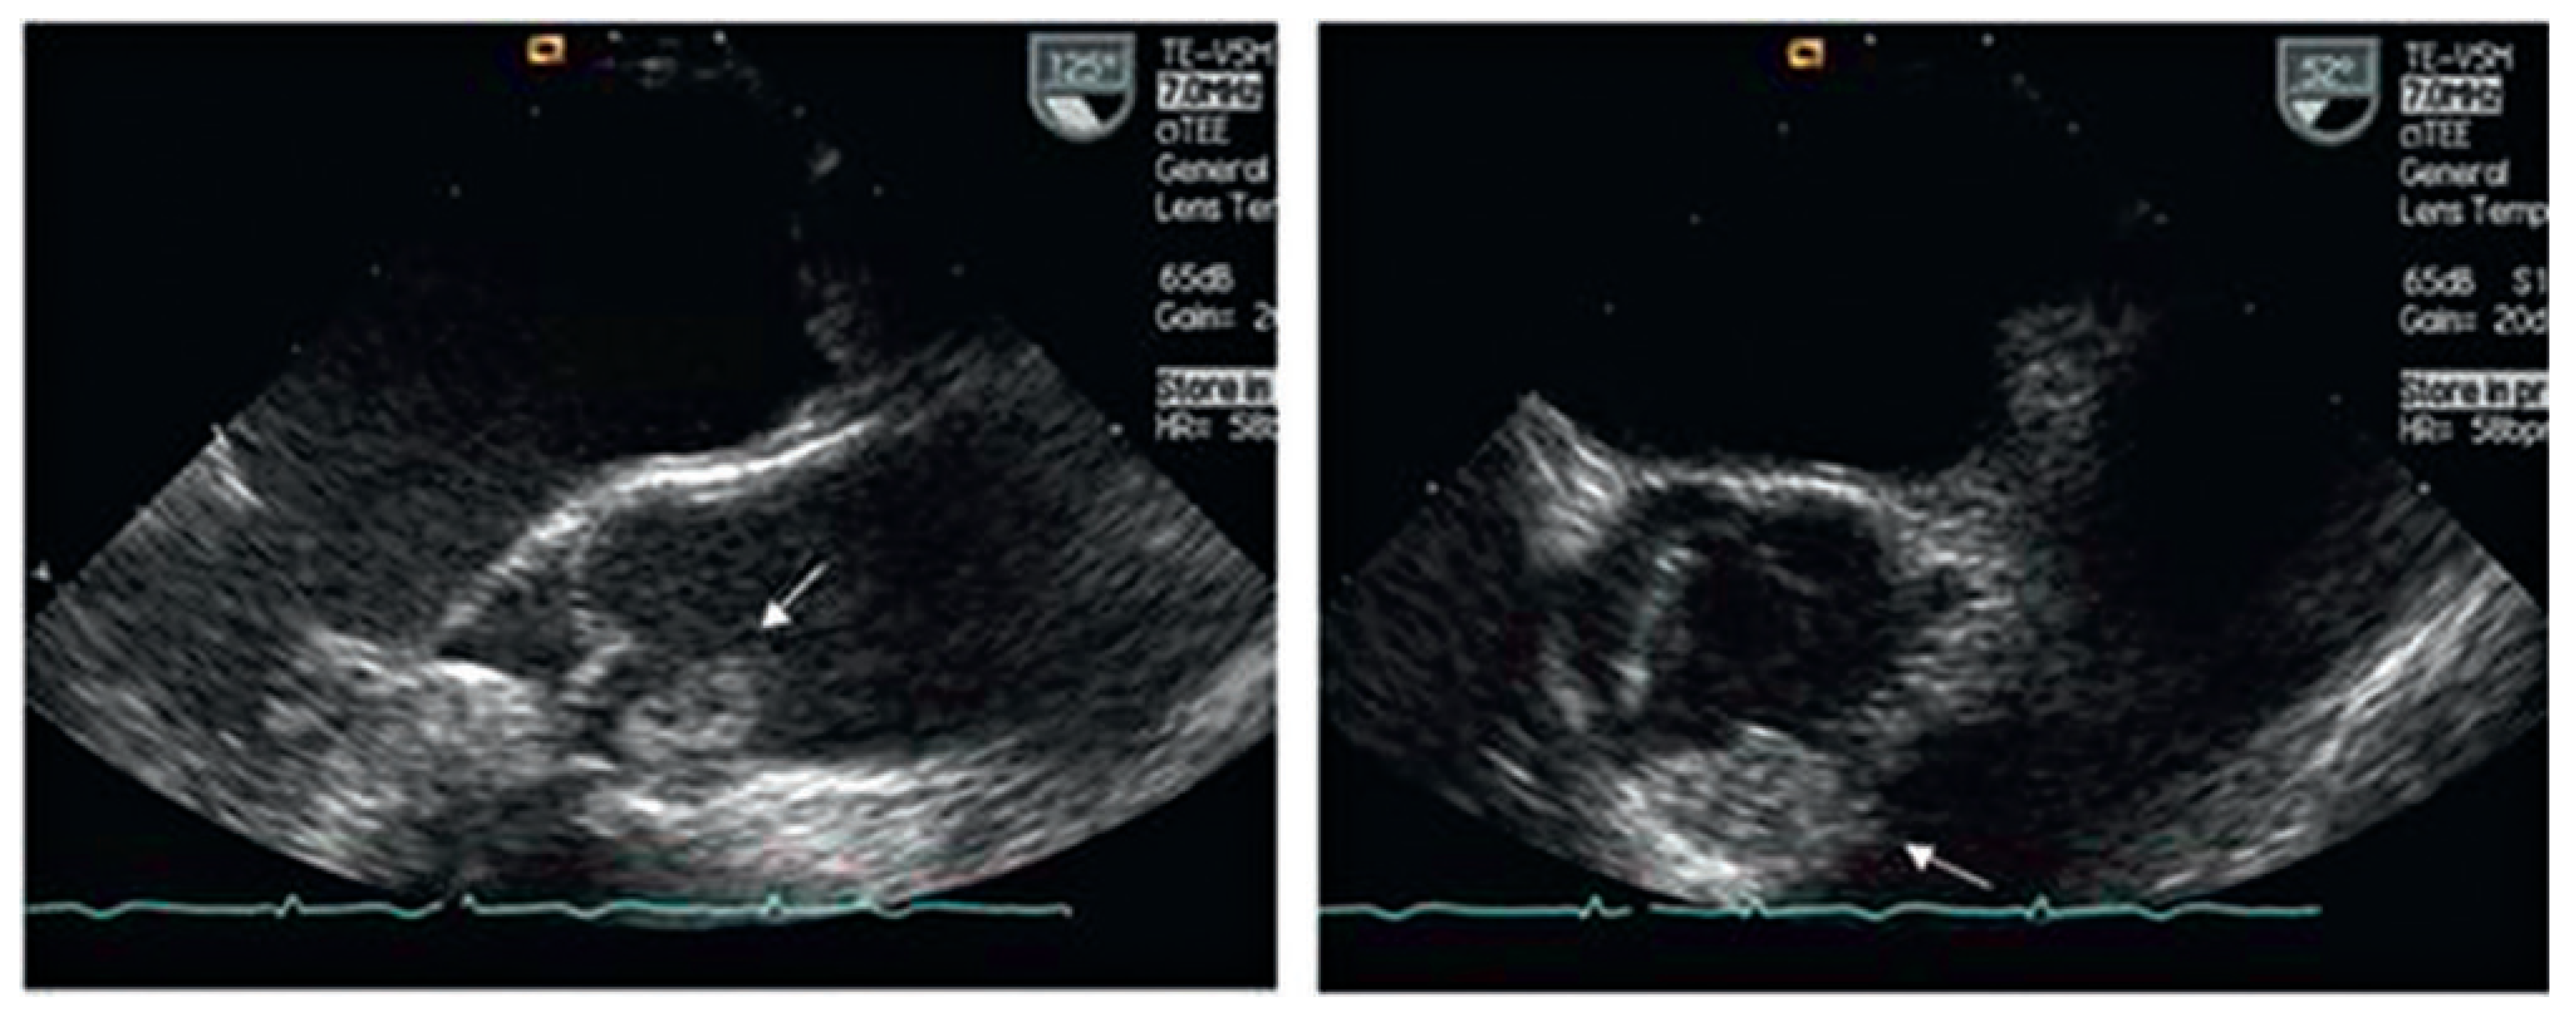

Case report 2: malignant myxoma

- Bernet, F.; Stulz, P.; Carrel, T. Long-term remission after combined resection, chemotherapy and irradiation of a metastatic left atrial myxoma. Ann Thorac Surg. 1998, 66, 1791–1792. [Google Scholar] [CrossRef] [PubMed]